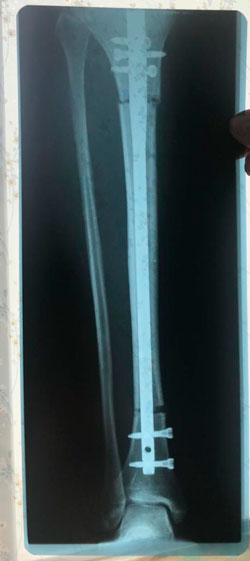

рентген снимки агрессивной, одномоментной методики исправления деформации

Результат этой работы, в исходнике :shock:

Так, пытались исправить деформацию ног в одной из Клиник Екатеринбурга.

рентген перед снятием аппаратов

Дата операции - 31.07.2020

Дата снятия аппаратов - 25.11.2020